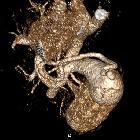

Splenic

arteriovenous fistula - Splenic vein aneurysm. Splenic vein aneurysm.